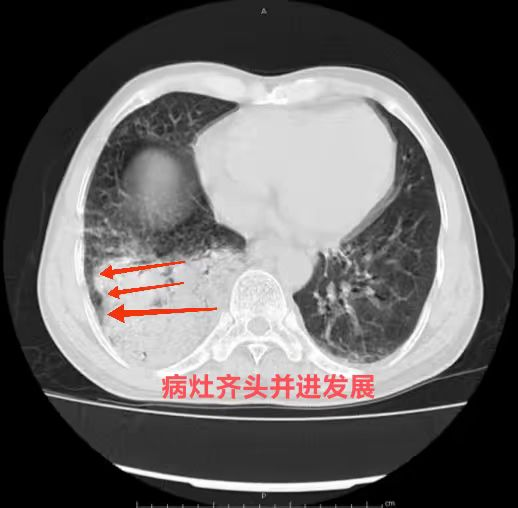

4.  大片病灶是否有齐头并进的特点?

肺炎链球菌肺炎多为肺泡性肺炎,少数血播肺炎链球菌肺炎好发于老年人及免疫力低下人群,PCT 明显增高。影像上,早期在血管炎的基础上仍能见到按肺小叶充填及闲置的表现(肺泡性肺炎的表现),而大片实变影已不能分辨是否为血管炎(病灶边缘磨玻璃仍可看出血管炎),在肺尖段不会占据整个层面(与铜绿假单胞菌肺炎不同),而在下肺往往表现为齐头并进的特点,分布上多上肺优势。